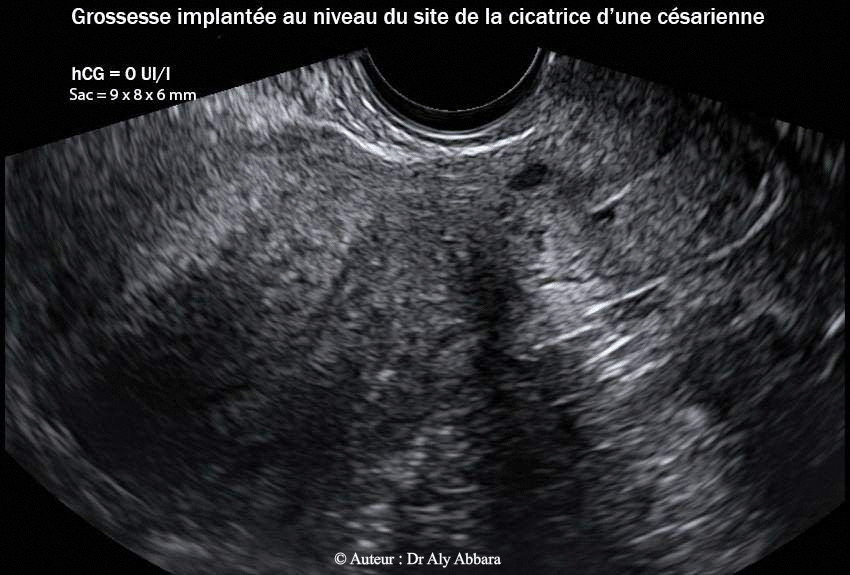

• Images échographiques par voie endovaginale montrant un sac gestationnel d'une grossesse débutante et partiellement intramurale, implantée dans le site de la cicatrice de l'hystérotomie segmentaire transversale d'une ancienne césarienne.

• L'aspect du sac gestationnel au 23e semaine post traitement médical par méthotrexate : il mesure 9 x 8 x 6 mm de diamètres (= 0,23 cm3) ; le dosage de β-hCG plasmatique = 0 UI/l.

15.03.2013 = (J162) = 23+1 S à 0 UI/l 9 x 8 x 6 mm = 0,23 cm3  J0